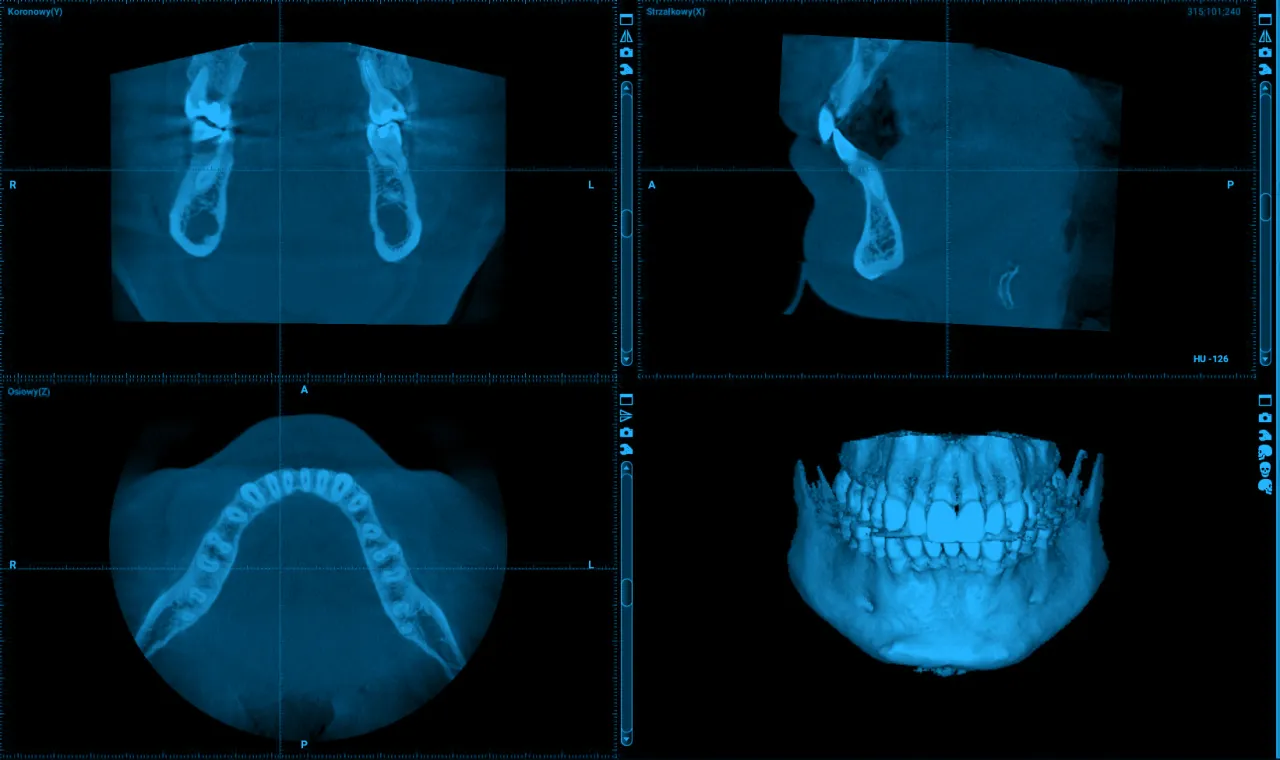

Tomografia 3D (CBCT): diagnostyka dla najtrudniejszych przypadków

W najbardziej skomplikowanych przypadkach, kiedy potrzebuję maksymalnej precyzji, sięgam po tomografię stożkową, czyli CBCT. To badanie oferuje trójwymiarowy obraz struktur jamy ustnej, co daje mi niezrównaną dokładność. Wykorzystuję ją przy podejrzeniu pęknięć korzenia, które są trudne do uchwycenia na standardowym RTG, do precyzyjnej oceny rozległych zmian zapalnych, planowania skomplikowanych ekstrakcji, a także przed zabiegami implantologicznymi. Obraz 3D pozwala mi zobaczyć problem z każdej perspektywy i zaplanować leczenie z chirurgiczną precyzją.